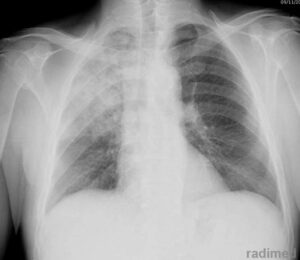

Nell’immagine in alto a destra è possibile apprezzare la radiografia di una presenza di aria tra il fegato e il diaframma come conseguenza di uno pneumoperitoneo. Nella radiografia si vede anche una banda scura di aria tra il cuore e la zona polmonare per via del passaggio di aria dal peritoneo al mediastino.

Anche nell’immagine di sinistra si vede la banda scura per via del passaggio di aria nel mediastino (frecce gialle più in basso).

Nella freccia gialla più alta della seconda immagine possibile apprezzare anche una massa di aria localizzata nel tessuto sottocutaneo.